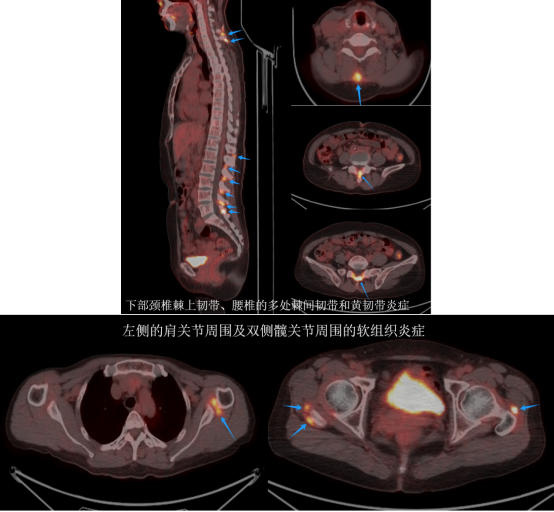

至于彭女士腰背部和肩关节周围的疼痛,PET/CT影像给出了明确的解答:这些疼痛源于多部位的软组织炎症,与结节性硬化症无关。接下来,彭女士需要进一步结合临床检查,排查是否存在风湿免疫性因素,并进行相应的治疗以缓解疼痛。

经过仔细的分析,医生们得出了结论:彭女士头部左侧侧脑室旁、双侧侧脑室室膜下多发大小不等的钙化结节,双肺多发磨玻璃结节及实性结节影,符合肺多发小结节样肺泡细胞增生的特征;同时,她的颅骨、胸骨、脊椎、骨盆骨等等多处存在骨质增生硬化的改变,双肾多发囊肿,左侧肾上腺存在结节。然而,这些病变在PET/CT图像上均未显示出葡萄糖代谢的异常增高,这意味着这些病变很可能并非恶性病变的多发转移。